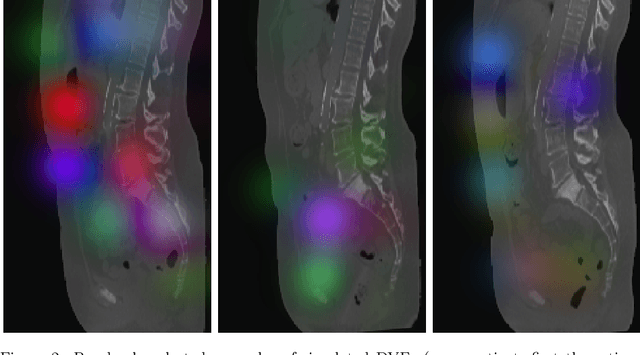

This study investigates the use of the unsupervised deep learning framework VoxelMorph for deformable registration of longitudinal abdominopelvic CT images acquired in patients with bone metastases from breast cancer. The CT images were refined prior to registration by automatically removing the CT table and all other extra-corporeal components. To improve the learning capabilities of VoxelMorph when only a limited amount of training data is available, a novel incremental training strategy is proposed based on simulated deformations of consecutive CT images. In a 4-fold cross-validation scheme, the incremental training strategy achieved significantly better registration performance compared to training on a single volume. Although our deformable image registration method did not outperform iterative registration using NiftyReg (considered as a benchmark) in terms of registration quality, the registrations were approximately 300 times faster. This study showed the feasibility of deep learning based deformable registration of longitudinal abdominopelvic CT images via a novel incremental training strategy based on simulated deformations.